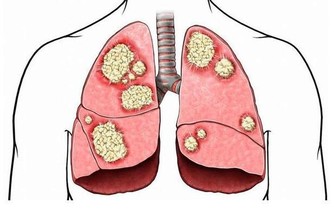

維生素B12缺乏症是世界上最常見的營養缺乏症之一,特別是在老年人中。維生素B12在保持身體的神經和血細胞健康是非常重要的。因此,當這種維生素水平不足時,身體就會受到影響。